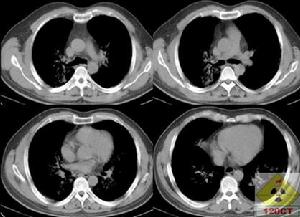

典型的胸片表現是雙肺對稱的肺泡填充性陰影,肺門旁的浸潤陰影延伸至外帶,呈“蝴蝶狀”分布,雙肋膈角往往不受累及。可是多數的PAP病例報導PAP的胸片沒有上述典型的特徵,因此X線胸片的表現通常不具有特異性。胸部HRCT能清晰地顯示肺部受累的範圍和特點。磨玻璃影與正常肺臟分界明顯,呈“地圖”樣分布;小葉內和小葉間隔增厚,呈多角形,稱為“鋪路石征”;或者表現為大片的實變影伴支氣管充氣征,周圍環繞著磨玻璃影。極少數病例有肺間質纖維化的表現,往往是疾病晚期。這些病變的程度和範圍與肺功能以及肺臟氣體交換障礙密切相關。